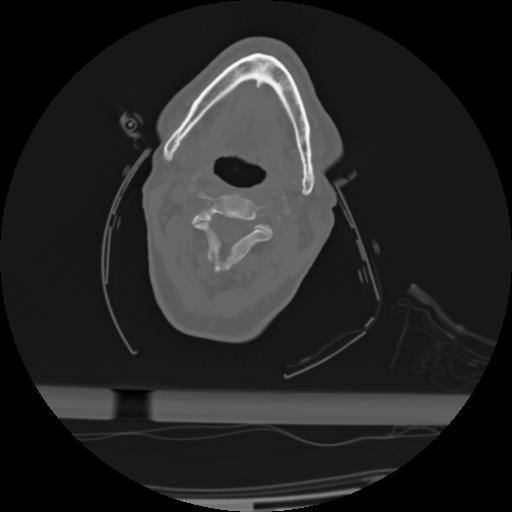

21 ANGIO,CE,Axial,3.0,ANGIO,,